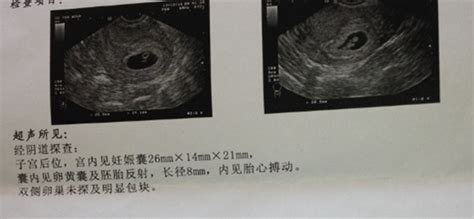

怀孕8个月胎儿b超图

怀孕8个月胎儿彩超图

怀孕8个月的B超数据

怀孕8个月胎儿B超数据